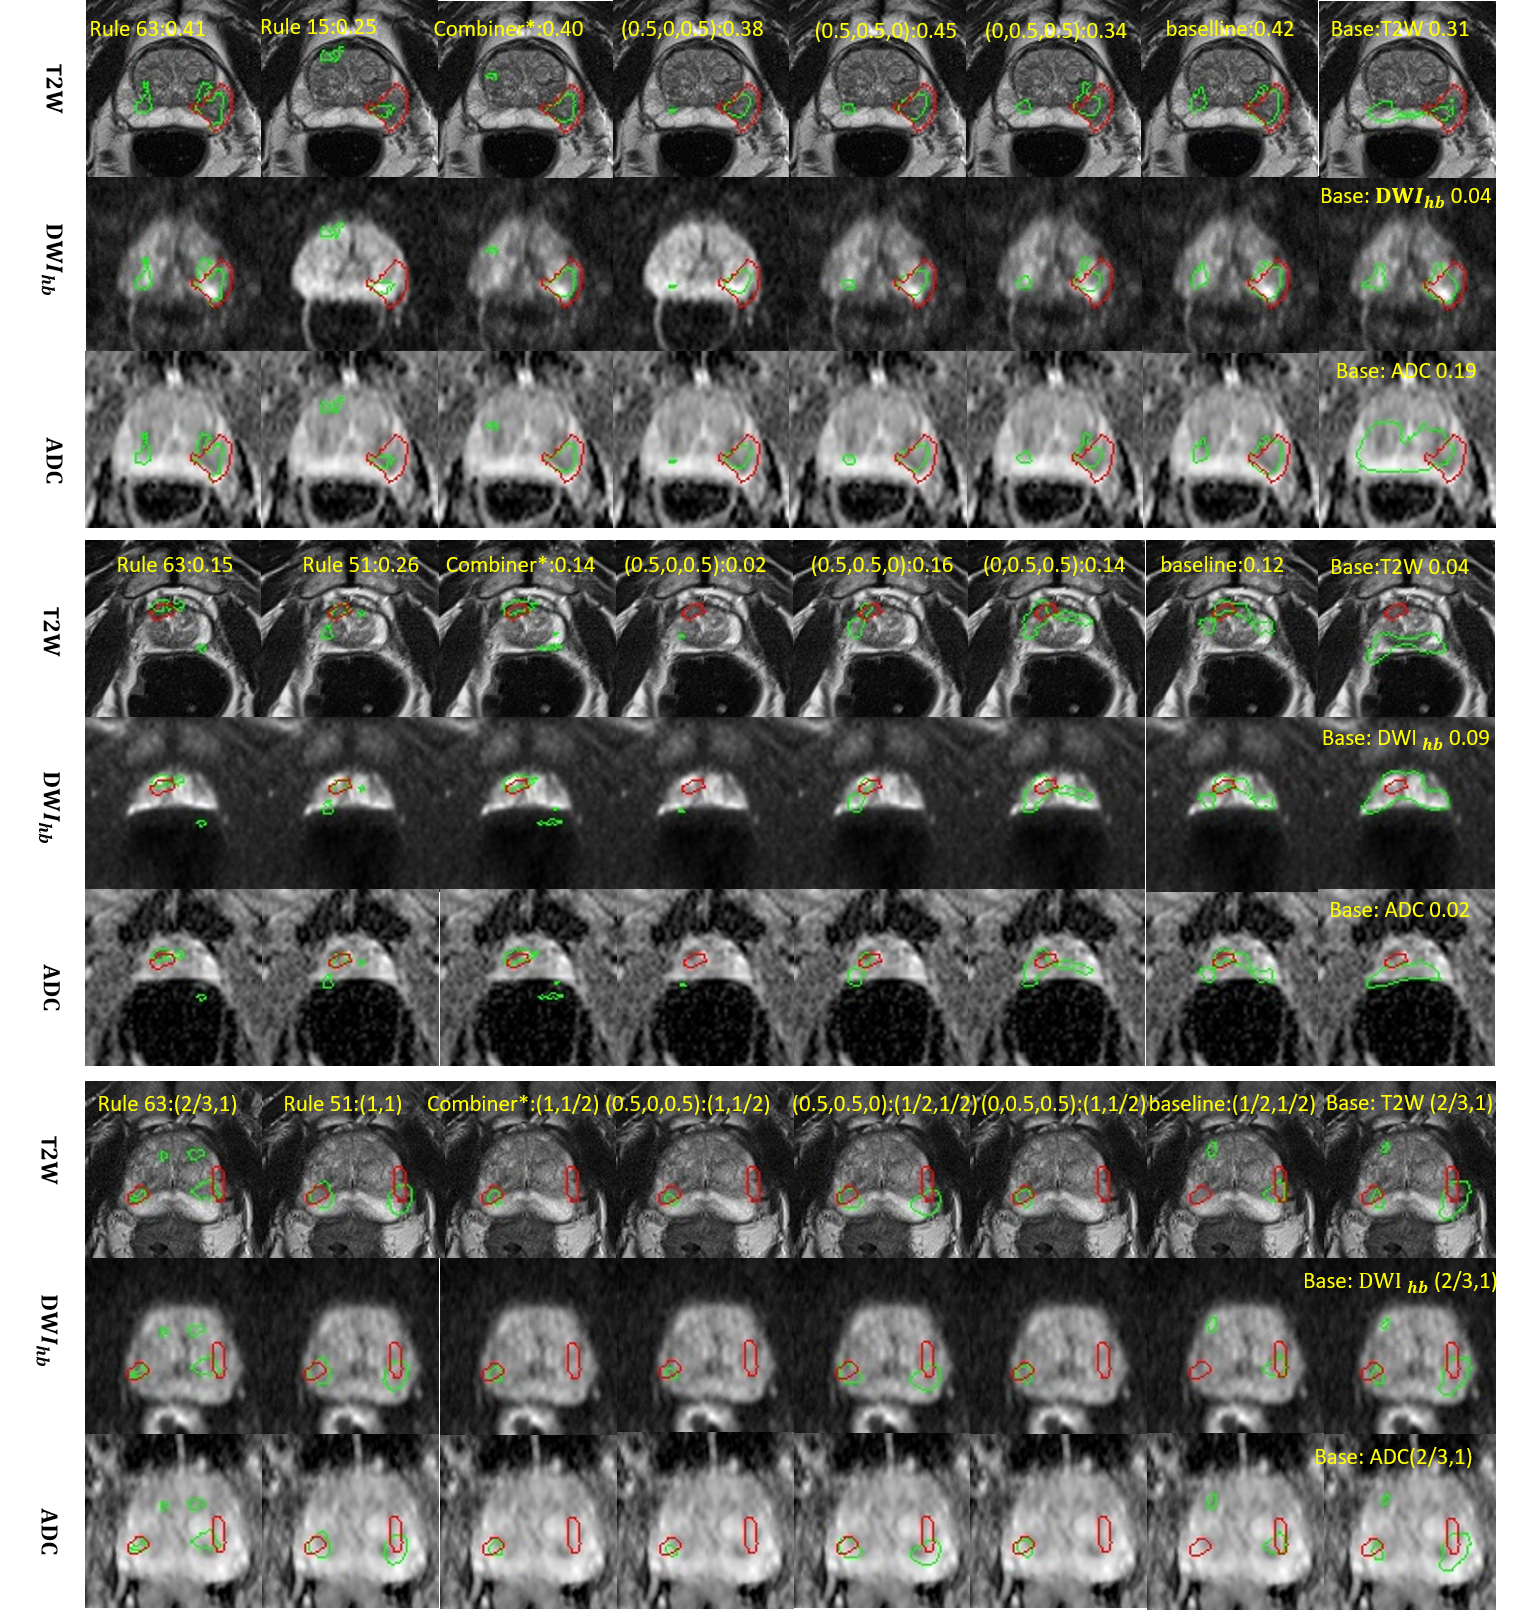

Figure 4: The first and second row of figures compared the DSC between Combiner and HyperCombiner based on UNet backbone in terms of the linear mixture and nonlinear stacking models, respectively. Note that x𝑥x coordinate was the No.RuleNo._{Rule} of randomly selected combinations of hyperparameters.

Refer to caption

5.2.4 The HyperCombiner networks

The validity of the HyperCombiner networks is bench-marked by the segmentation metrics based on the Combiner networks for permuted hyperparameter values and different lesion locations, as shown in 4. The randomly selected ten combinations of hyperparameters were used to demonstrate the DSC values between the HyperCombiner and Combiner networks at the same hyperparameter values. The results showed that, in general, the single HyperCombiner networks are capable of replacing different Combiner networks trained with varying hyperparameter values.